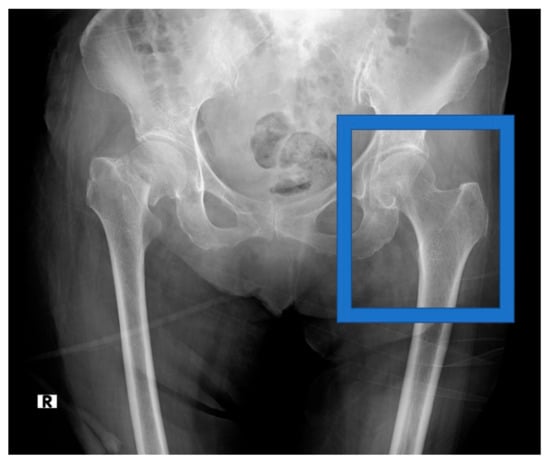

The side of the hip measured using DXA was selected as the cropped side in the pre-analysis image-cropping method. The lines of the femoral head and the inferior margin of the lesser trochanter were selected and cropped to include the lines of the femoral head and the inferior margin of the lesser trochanter, as illustrated in Figure 1, as the range cropped with the DXA measurement. The cropped area imitated the osteoporosis diagnosis range obtained using the DXA method. The cropped images were saved in PNG format. None of the orthopedic surgeons who performed the cropping were informed of the patient’s BMD status.

Figure 1.

Hip radiograph before analysis, showing region of interest that was cropped.